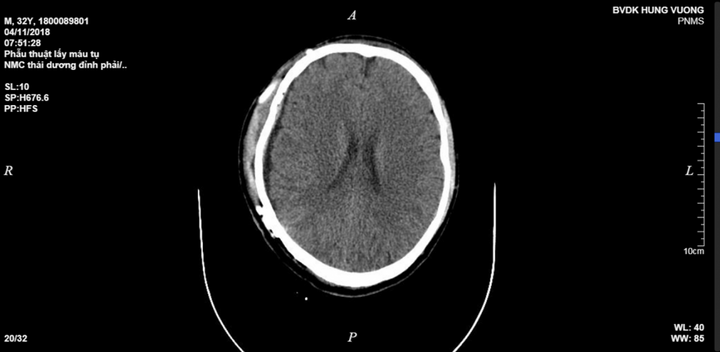

Anh N.P. (32 tuổi, ở Yên Bái) ngã lao xuống đất, tụ máu não, tính mạng khá nguy kịch, vừa được các bác sĩ cứu sống.